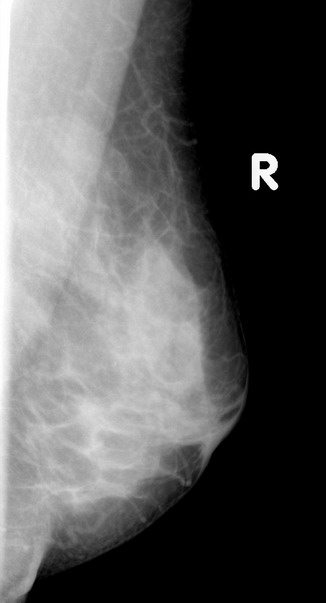

标题: x2364:女,45岁,乳房胀痛,触及硬块求诊 [打印本页]

女,45岁,乳房胀痛,触及硬块求诊

体查:左侧乳房可触及多个硬块,活动度可,无压痛

本人对于乳腺在太多的拿不准,发现乳腺太难看了,我的意见是:

1,左侧乳腺外上象限肿块样影,腺体增生?乳腺纤维瘤?

2,右乳外下象限局部密度增高明显,建议必要时彩超检查除外其他。

3,双侧乳腺小叶增生。

乳头稍凹陷,乳晕皮肤增厚,乳腺非对称性致密,未见明显肿块影,未见异常粗大血管和淋巴结

考虑双侧乳腺小叶增生症.

乳腺非对称性致密,未见明显肿块影,未见异常粗大血管和淋巴结